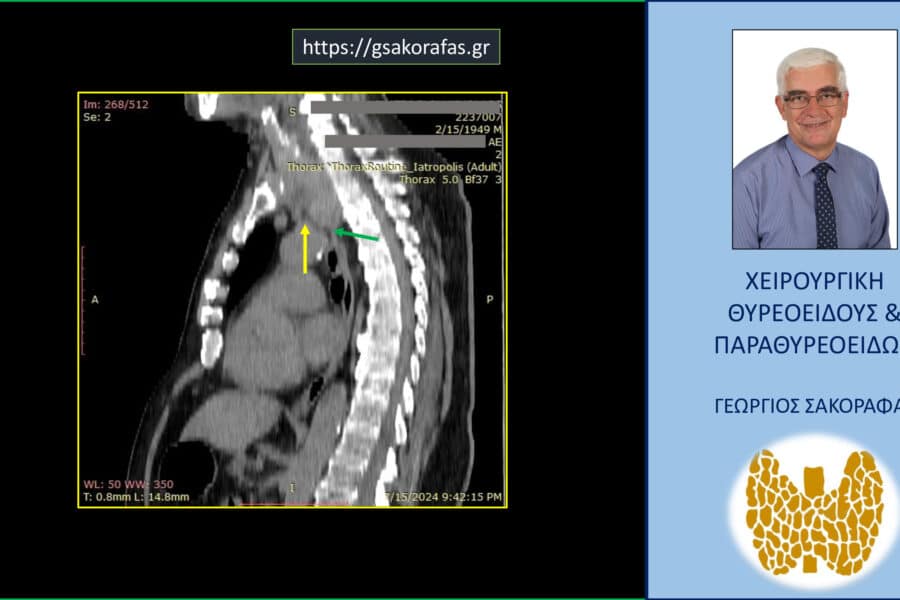

Όζοι θυρεοειδούς και συμπληρωματική θυρεοειδεκτομή (completion thyroidectomy) – με αφορμή ασθενή μας Παρουσίαση ασθενούς Αιτία…